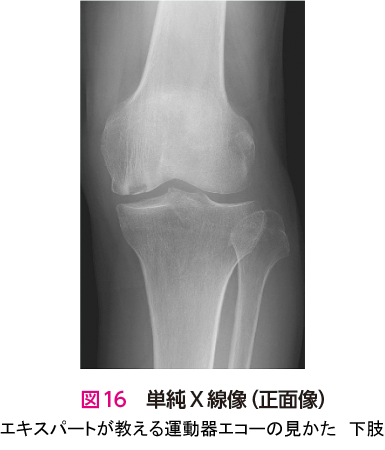

症例 6大腿骨内顆骨壊死(脆弱性骨折)